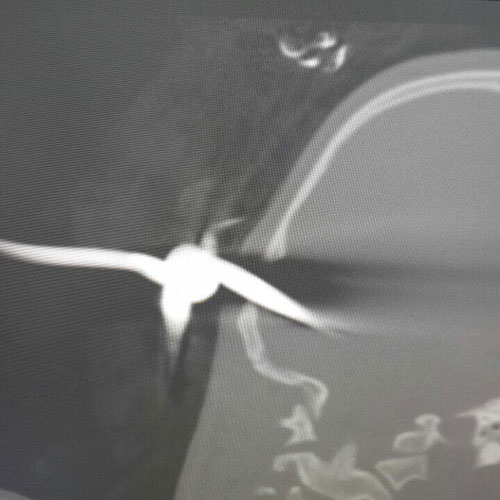

نجح فريق طبي جراحي بمستشفى الملك خالد بتبوك في إنقاذ حياة طفل يبلغ من العمر 11 سنة أصيب بنزيف في الرأس جراء اختراق «زرادية» لجمجمة الرأس، وفور وصول الطفل لقسم الطوارئ أجريت له الفحوصات، حيث أظهرت الأشعة المقطعية وصول جزء من الأداة الى داخل المخ والحاقها الضرر بالأوردة الدموية.

وتم إخضاع الطفل لعملية جراحية عاجلة أشرف عليها فريق طبي متخصص في جراحة المخ والأعصاب، حيث تم استخراج «الزرادية» من رأس الطفل وتم إيقاف النزيف بنجاح في حين وصفت حالة الطفل الصحية بالجيدة.